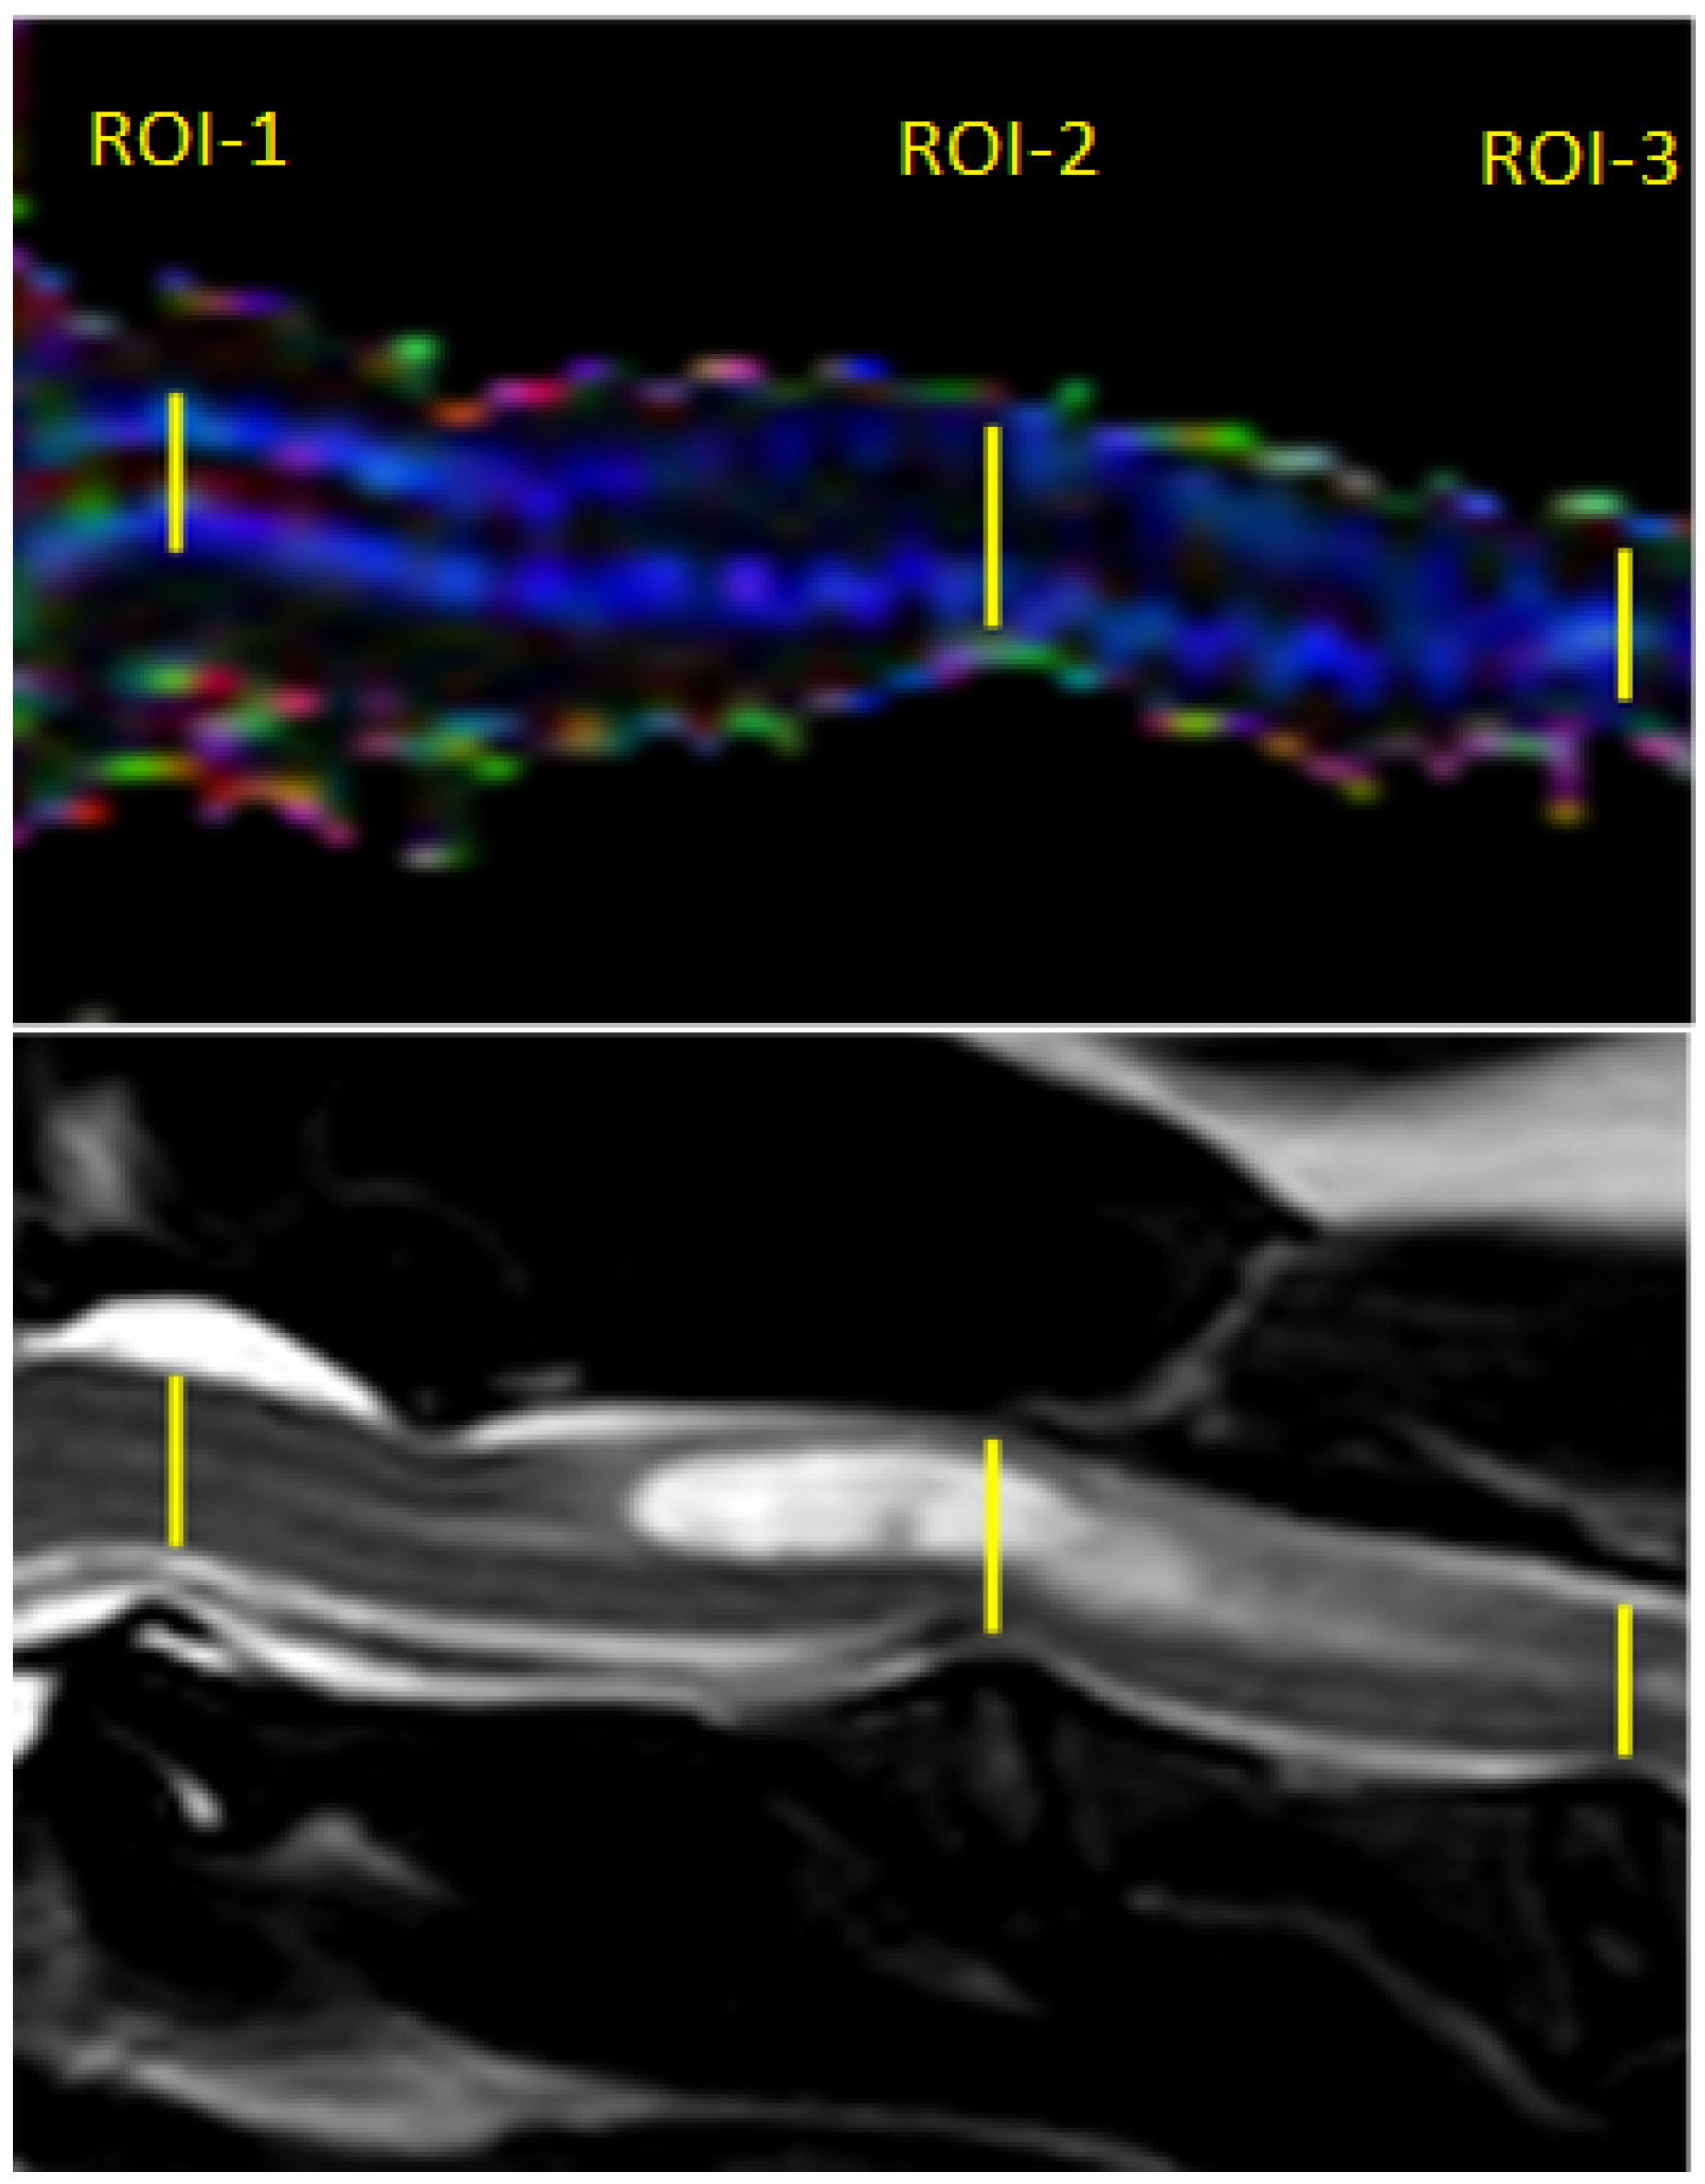

Post-processing of the DTI data was performed using Philips DTI Fiber Trak Software. The reconstruction of white matter tracts was performed by manually drawing the region of interest (in linear shape) from the occipital bone to the fourth cervical vertebrae on the sagittal plane. ADC and FA metrics were measured on ADC and FA maps using manual placement of 3 regions of interest (ROIs) in the centre of the cervical spinal cord in the midsagittal plane at the level of 3 intervertebral discs between C1 and C4 (ROI-1 at C1-C2, ROI-2 at C2-C3, ROI-3 at C3-C4); ROIs were linear in shape and similar in size. In the study group, ROI-1 was always applied on the spinal cord without visible pathological changes in standard structural MRI protocol, while ROIs 2 and 3 included the syrinx (Figure 2).

Figure 2.

Sagittal T2-weighted MR image and FA map of the spinal cord showing ROIs placement within the spinal cord of the SM dog.